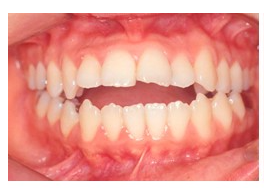

정상적인 교합은 윗니가 아랫니를 덮어야하지만

아래 치아가 위에 앞니보다 더 앞으로 나와있는 경우에요~